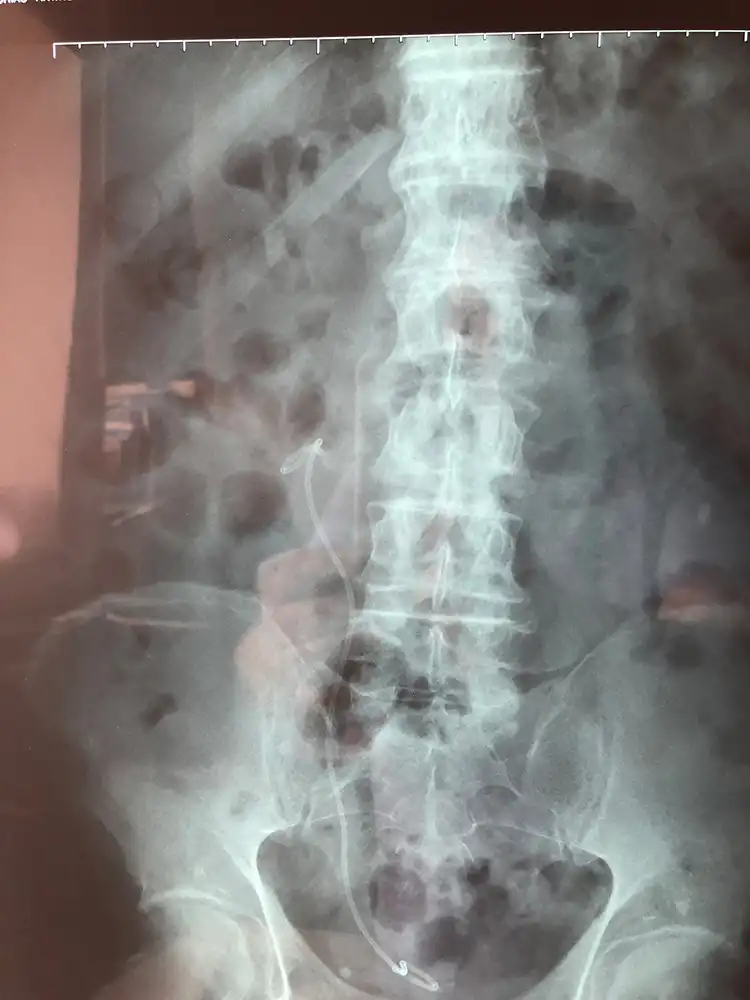

Περιστατικό 1, Ημιάκαμπτη Ουρητηρολιθοθρυψία (semi-rigid URS)

Ασθενής με ευμεγέθη λίθο στο άνω τριτημόριο του αριστερού ουρητήρα, ο οποίος φέρει νεφροστομία λόγω αποφρακτικής ουροπάθειας (Φωτογραφία 1), αντιμετωπίστηκε με laser ουρητηρολιθοθρυψία με ημιάκαμπτο ουρητηροσκόπιο και τοποθέτηση pig-tail με ταυτόχρονη αφαίρεση της νεφροστομίας (Φωτογραφία 2, 1η ημέρα μετεγχειρητικά). Η τρίτη φωτογραφία είναι στις 15 ημέρες πριν την αφαίρεση του pig-tail.